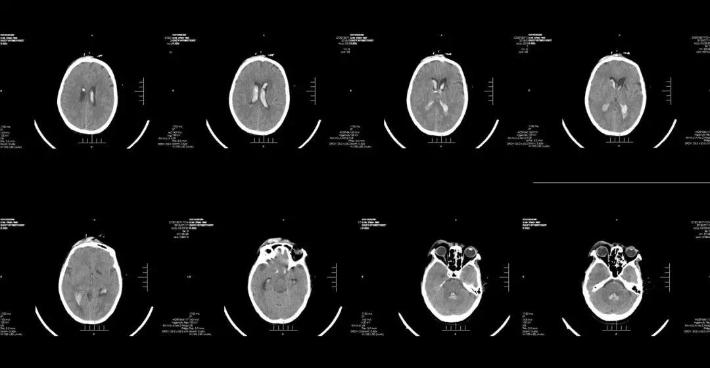

术后1周复查头颅CT

腰椎穿刺术脑脊液逐渐恢复至清亮。患者恢复良好,神志清楚,四肢肌力肌张力正常,未遗留神经功能缺损症状。

总 结

✔Enterprise支架释放后,右侧大脑前动脉A1段未显影,考虑可能为支架打开后,对病变段血管的修复及一定血流导向作用,大脑中动脉前向血流增加,而原本纤细的左侧大脑前动脉A1段血流减少,对侧大脑前动脉通过前交通动脉向左侧大脑前动脉A2段主流供血,由于血流对冲作用至左侧大脑前动脉A1段不显影。后对侧评估前交通开放,对侧代偿良好,结束手术。术后患者亦未再出现新的神经系统体征,肢体活动及语言功能恢复良好,1周后头颅CT未见新发梗死灶。